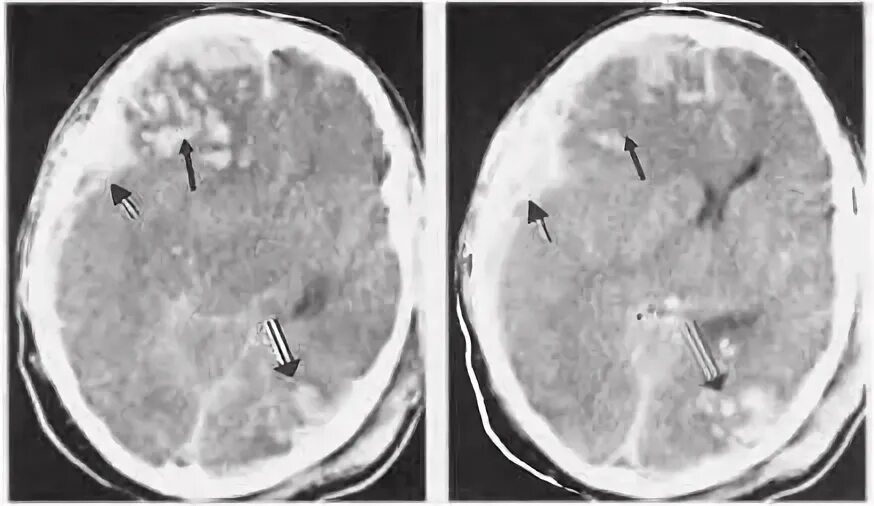

Ушиб мозга на кт